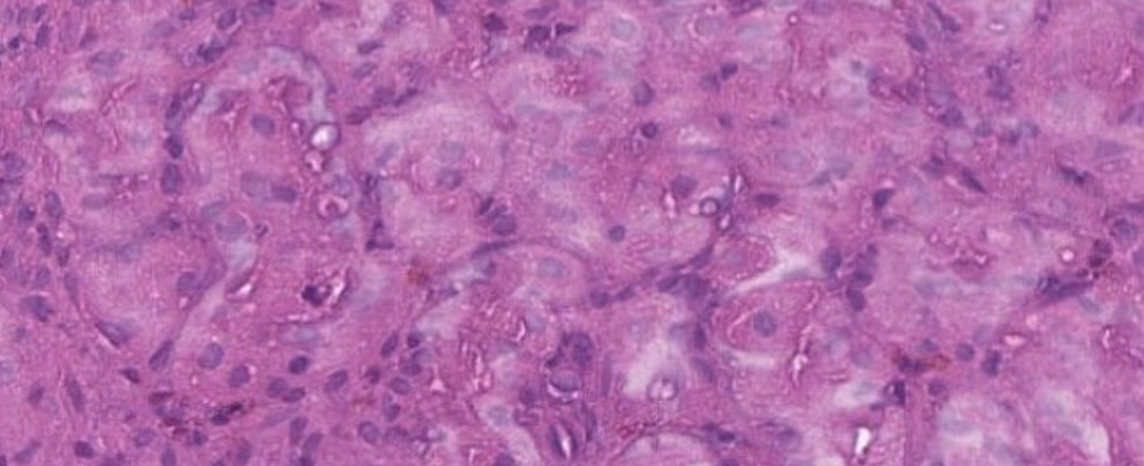

Варианты разные: грязные реагенты (ксилол), плохо протопленные стёкла, недостаточная обработка ткани на этапах фиксации и проводки... Но многие ли из нас задумывались о температуре в помещении во время окраски препаратов?

☝️А ведь температура самым непосредственным образом влияет на скорость реакции (см. правило Вант-Гоффа http://ximik.biz/znamenitie-himiki.-nobelevski…). Если температура ниже, химические реакции замедляются.

☝️Парафин становится более твёрдым при низких температурах (что следует из его физических свойств), а ксилол медленнее реагирует с ним при температуре ниже 20оС. На этом набито немало шишек, и причины тому - открытые окна, отключение отопления в холодное время года или яростные любители холода в помещении.

☝️Кстати, по СанПиНу для комнат с медицинской техникой температура составляет 22-24оС в холодный период года и 21-23оС в тёплый период ;)

И всё же, если нормы по каким-либо причинам не были соблюдены, не всегда можно быстро нагреть помещение.

☝️Некоторые лаборатории выходят из положения таким образом: используют подогрев ёмкостей с ксилолом (если такое предусмотрено в стейнере), или просто ставят закрытую бутыль с этим реактивом в термостат на ~полчаса при 37оС, а после используют для депарафинизации.

👍При таких условиях реакция протекает быстрее. Конечно, если ксилол не насыщен парафином.

☝️Поэтому важно не только следить за температурой, но и вовремя менять реактивы. А так же периодически контролировать предыдущие этапы, потому что такие проблемы обычно комплексные.